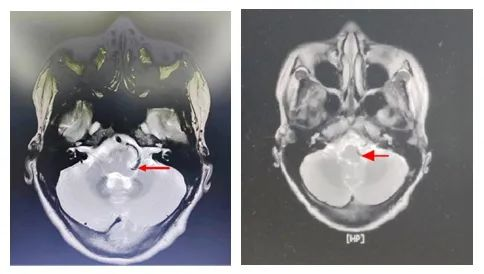

近日,31岁的吴女士便因为该疾病严重影响日常生活与工作。吴女士约3年前明显诱因出现左眼睑抽搐,间断发作,持续约几秒钟,开始可自行缓解,于3月余前加重,伴左嘴角抽搐,发作次数较前增多,为寻求进一步治疗来到我院神经外科一区就诊。患者入院后完善颅脑MRI提示延髓左侧缘椎动脉压迹,经神经外科学术带头人王鹏手术团队评估并结合磁共振检查诊断为左侧面肌痉挛,且左侧面神经与左侧椎动脉关系密切。

▲延髓左侧面神经根部血管压迫明显